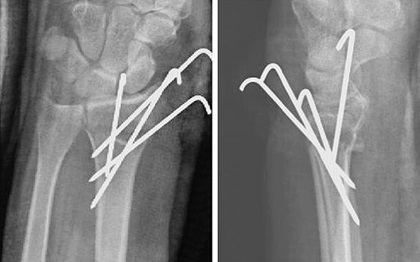

With percutaneous pinning of a distal radius fracture, a closed reduction of the fracture is performed and then percutaneous pins (thin wires) are inserted through the skin and into the bone to maintain alignment.

The wrist is then placed in a cast for 3-6 weeks. This is less invasive than open fixation as no incision is required, the pins are simply pushed through the skin into place - they may be completely buried or may extend out of the skin.